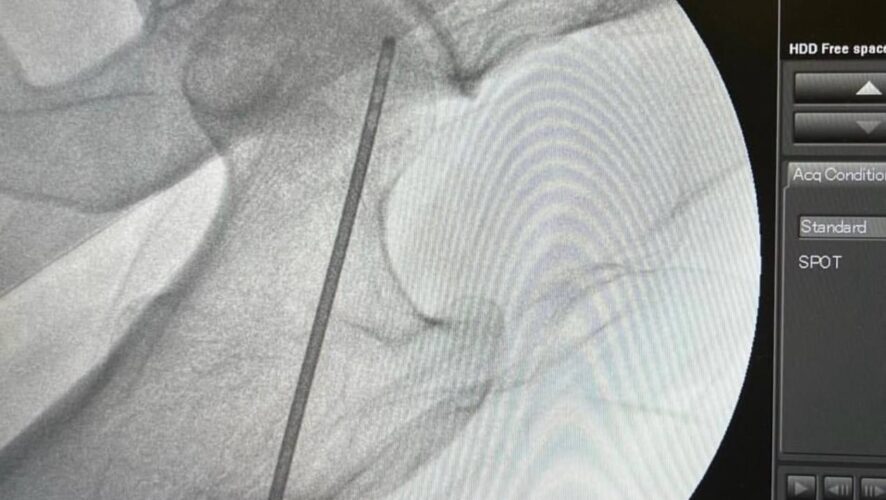

Заведующий отделением травматологии №1 Гамиль Гарифуллов предложил методику, которая дает возможность отсрочить замену суставов. Травматологи просверлили канал до очага некроза и ввели в него стволовые клетки. Перед операцией травматологи забирают жировую ткань с передней брюшной стенки, центрифугируют и поучают стромально-васкулярные клетки. Смешивают их с плазмой пациента и этот «коктейль» вводят в очаг некроза.